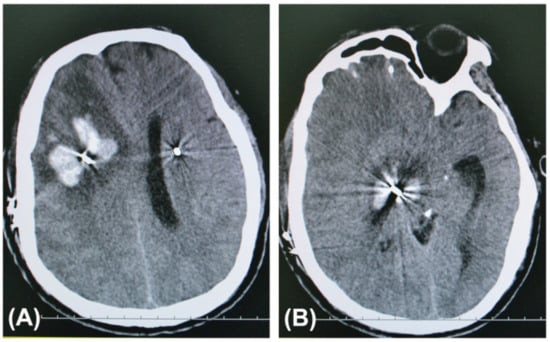

Statistically significant differences in the numbers of both patients and leads associated with symptomatic ICH were observed between the trajectory planning group and the non-trajectory planning group (p < 0.05). No symptomatic ICH patients had microelectrode recordings (MER), which were seldom used in this series. All bleeding cases were PD patients with the STN as their targets. The details of the patients with symptomatic ICH in the non-trajectory planning group were published in our previous article []. In the trajectory planning group, two patients developed asymptomatic ICH as observed on routine postoperative CT images. In the non-trajectory planning group, regular postoperative imaging was not performed in 186 patients, whose cranial CT scan was not performed on the first day after operation. The symptomatic ICH cases after DBS surgery in the two groups are shown in Table 3. CT images of a PD patient with symptomatic ICH after DBS surgery in the non-trajectory planning group are shown in Figure 1.

Figure 1.

Axial computed tomography (CT) slices at the hemorrhage sites taken after the health of a 53-year-old man with PD in the non-trajectory planning group deteriorated on the 6th postoperative day. He had suffered from a headache for a few days before falling into a coma. His hematomas were along the trajectory of the definitive electrode in the right frontal lobe (A), basal ganglia, and midbrain (B).